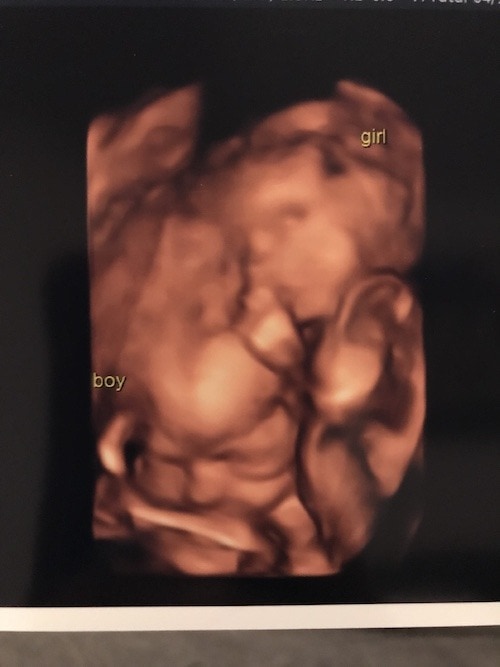

- Ultrasound Photos at 24 Weeks Pregnant With Twins

Ultrasound Photos at 24 Weeks Pregnant With Twins